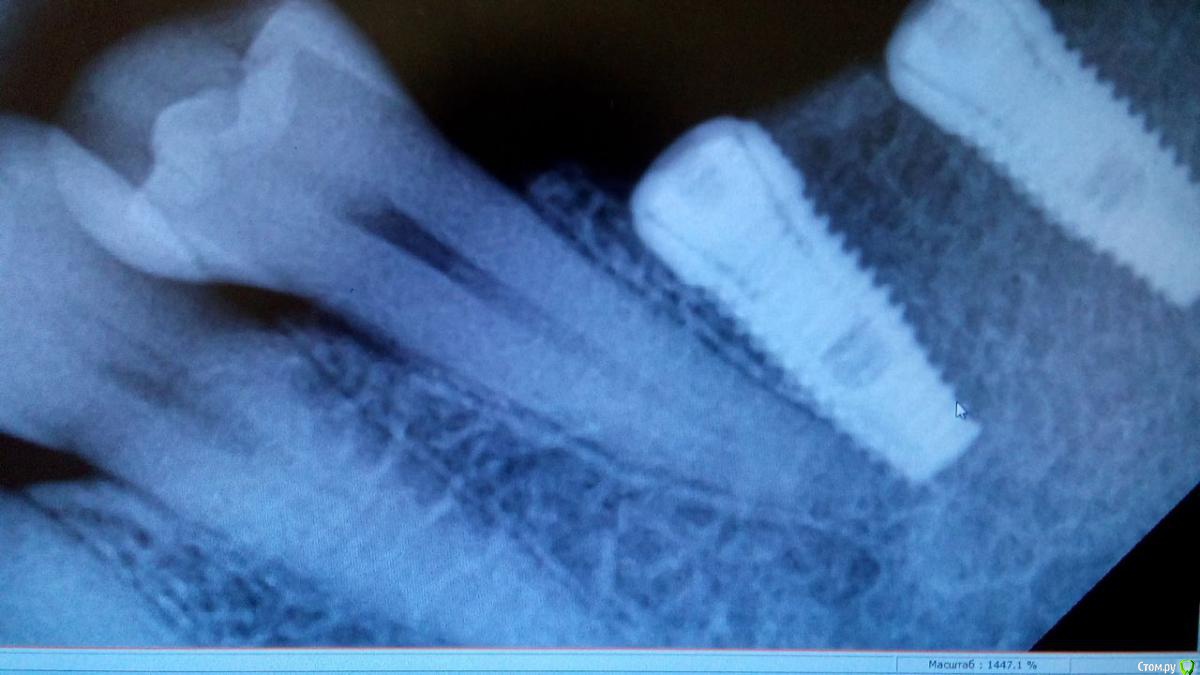

Bier Опубликовано 13 июня, 2015 Поделиться Опубликовано 13 июня, 2015 если со стороны зуба жалоб нет, то показаний к удалению имплантата нет никаких абсолютно. В коронарной части расстояние достаточное, а апикально - главное чтобы хитрута не было и все. 3 Ссылка на комментарий

Rafael_Gogyan Опубликовано 14 июня, 2015 Поделиться Опубликовано 14 июня, 2015 В данном случае не вижу особых проблем. Убирать имплантат (ИМХО) показаний нет. Ссылка на комментарий